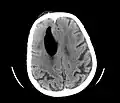

CT scans of patients with a tension pneumocephalus typically show air that compresses the frontal lobes of the brain, which results in a tented appearance of the brain in the skull known as the Mount Fuji sign.[1][2][3] The name is derived from the resemblance of the brain to Mount Fuji in Japan, a volcano known for its symmetrical cone. In typical cases, there is a symmetrical depression near the midline (such as the crater of a volcano), due to intact bridging veins.[3] Its occurrence seems to be limited to tension pneumocephalus (not occurring in pneumocephalus without tension).[4] The sign was first described by a team of Japanese neurosurgeons.[5]